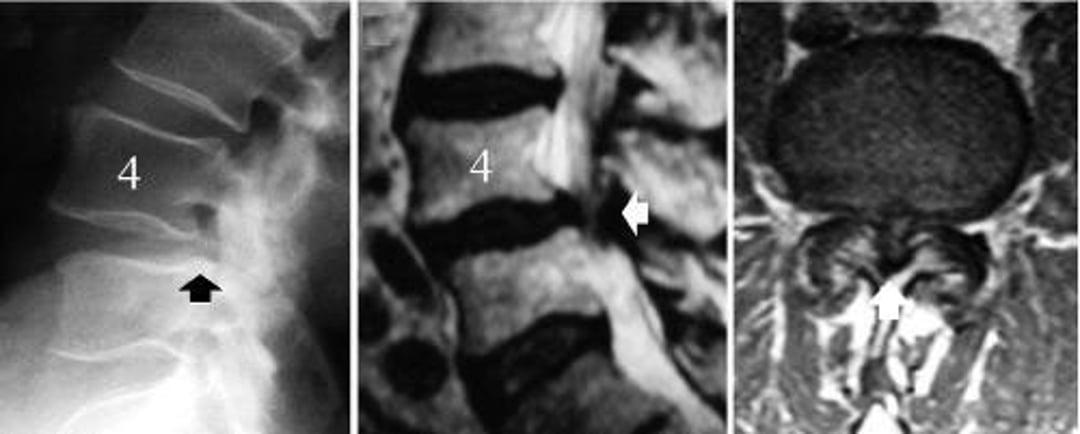

© Springer Science+Business Media

Os exames diagnósticos para estenose espinal lombar, quando necessários, são os mesmos que para a radiculopatia lombossacral, incluindo RM ou TC e estudos eletrodiagnósticos.